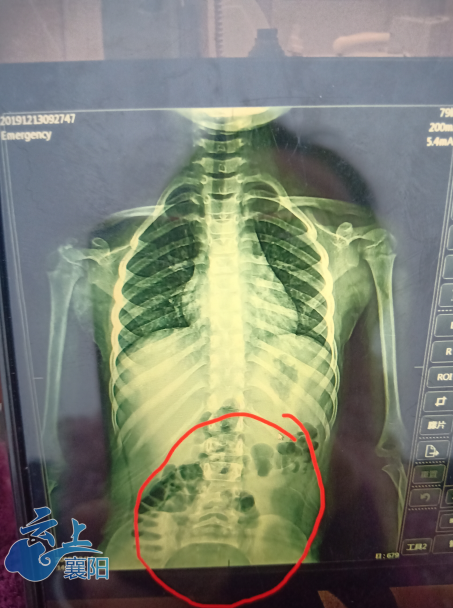

请各位专家帮我看看,我小孩16岁了,腰椎变形,有没有什么办法矫正,最好

女儿8岁,在医院照x光片,发现胸腰段脊椎略侧突畸形,严重吗?